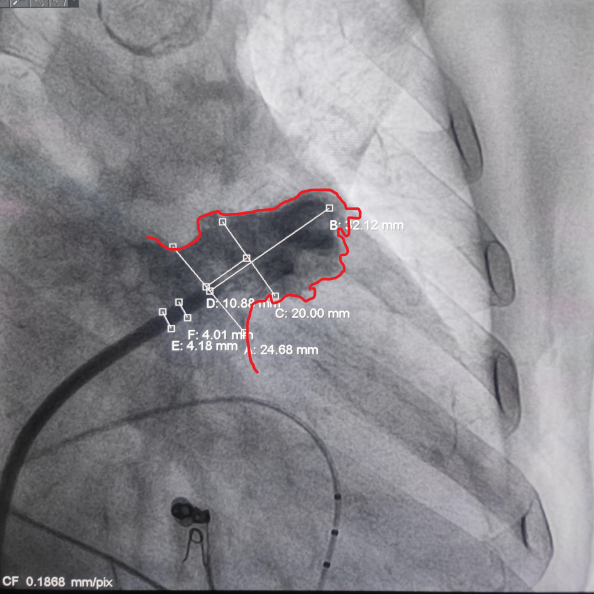

通过LAA造影和工作体位测量,结果显示患者左心耳开口直径为25mm,着陆区直径为20mm,深度为32mm;根据数据,手术团队决定选择Laager®封堵器2429型号进行后续操作;

工作体位造影

画线测量